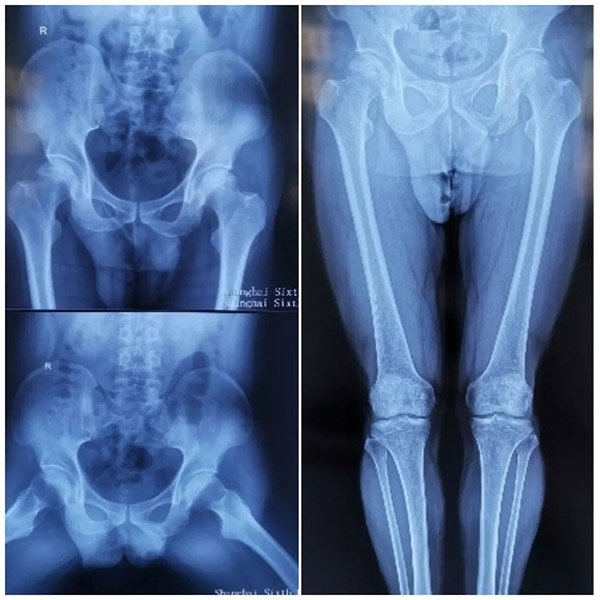

在黑龙江当地的医院,赵大哥接受了双侧髋关节MRI检查,发现双侧股骨头不规整,其内信号不均。压脂呈高信号,以左侧为主。检查意见为双侧股骨头缺血性坏死。

入 院后,经过进一步检查,赵大哥左侧腹股沟中点压痛阳性,左髋部外侧压痛阳性,轴向叩击痛阴性,左髋关节活动明显受限,“4”字征阳性,麦氏征阳性;右侧腹 股沟中段深压痛阳性,行走不受影响,但无法蹲踞或剧烈活动。双下肢皮肤感觉正常,两脚各足趾活动自如,足背动脉搏动有力,末梢血运正常。

在椎管内麻醉下,赵大哥接受了左侧股骨头坏死关节囊切开减压,滑膜切除,死骨剥除植骨,血管植入,PRP植入,髋-人字支具外固定术手术治疗。这也是沈阳六院开展的首例股骨头坏死的PRP植入保髋治疗。

术后,赵大哥整体状态良好,髋-人字支具持续外固定,切口皮缘对合良好,无渗出及异常分泌物,左下肢皮肤感觉正常,左踝关节及左脚各足趾活动自如,末梢血运正常。